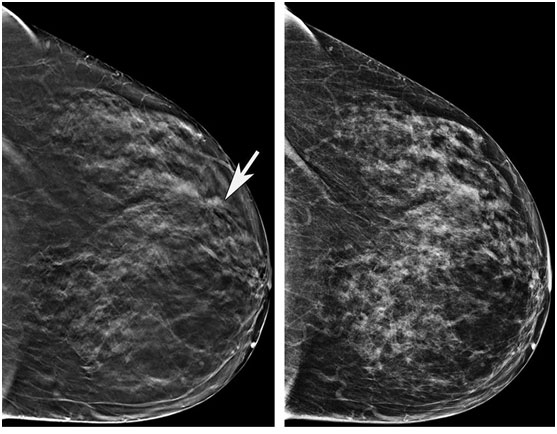

1.老年女性可從數(shù)字化乳房斷層合成技術(shù)進(jìn)行乳腺篩查中獲益(又稱三維乳房X光影像檢查)。

2.將15000多名接受二維乳房X光篩查的女性數(shù)據(jù)與20000多名接受三維X線篩查的婦女的數(shù)據(jù)進(jìn)行比較。二維檢查老年女性方面表現(xiàn)良好,但三維檢查更勝一籌。

近日發(fā)表在《放射學(xué)》雜志上的一項(xiàng)研究顯示:乳房X光檢查仍是65歲及以上女性乳腺癌篩查的有效方法,加上一種名為“斷層合成”的三維技術(shù)(DBT),可進(jìn)一步提高篩查效果。

乳腺癌是女性第一大癌癥,不同分期的乳腺癌預(yù)后差異巨大。研究表明,數(shù)字二維乳房X光影像(DM)可通過(guò)早期檢測(cè)降低乳腺癌相關(guān)死亡率。2011年,美國(guó)FDA已批準(zhǔn)了用于乳腺癌篩查的三維乳房X光設(shè)備。從那時(shí)起,它被廣泛用作二維乳房X光的輔助檢測(cè)。

這兩種方法在檢測(cè)癌癥方面都很有效,但與二維方法相比,三維篩查具有一些優(yōu)勢(shì),包括減少假陽(yáng)性檢出率。此外,三維乳房X光攝影術(shù)還具有更高的陽(yáng)性預(yù)測(cè)價(jià)值,更高的特異性(區(qū)分惡性和良性結(jié)果的能力)。

研究主要作者、MGH放射學(xué)家和哈佛醫(yī)學(xué)院放射學(xué)助理教授Manisha Bahl博士說(shuō):“乳房X光檢查在老年女性中表現(xiàn)良好,癌癥檢出率高,假陽(yáng)性率低,而三維乳房X光比傳統(tǒng)的二維乳房X光檢查效果更好。例如,三維檢查的異常解釋率(即拍過(guò)乳房X光片后被召回進(jìn)行額外檢查的女性的百分比)低于傳統(tǒng)的二維檢查。我們還發(fā)現(xiàn),用三維技術(shù)檢測(cè)到淋巴結(jié)陽(yáng)性的癌癥更少,這表明它能在更早期檢測(cè)到癌癥。”